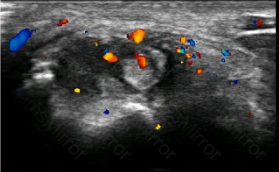

A woman with a history of long-standing rheumatoid arthritis presents with persistent, chronic wrist pain and swelling. What do the patient’s ultrasound images demonstrate?